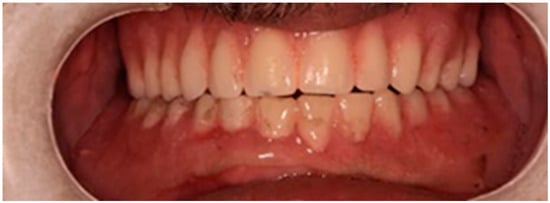

The restoration plan involved placing a bridge that connects the central incisors to the canines, along with an additional bridge spanning the first premolar to the first molar on each side of the maxillary arch. In the mandibular arch, the plan included three bridges: one connecting the lateral incisors bilaterally and another bridging the canines to the second premolars and first molars on each side (Figure 14 and Figure 15). Placing was confirmed using Panoramic radiographs obtained using the PantOs DG XP panoramic dental X-ray system (Fona S.r.l., Assago, Italy; CE 0051). The unit operates on a 230 V, 50/60 Hz input line with an 8 A fuse. Standard panoramic exposure parameters were applied (90 kVp, 10 mA, exposure time 14 s) following the manufacturer’s safety recommendations. A trained radiology technician performed all scans, and patient positioning was standardized using the built-in cephalostat support and light-beam alignment to ensure reproducibility of serial images.

Figure 14. The final prostheses.